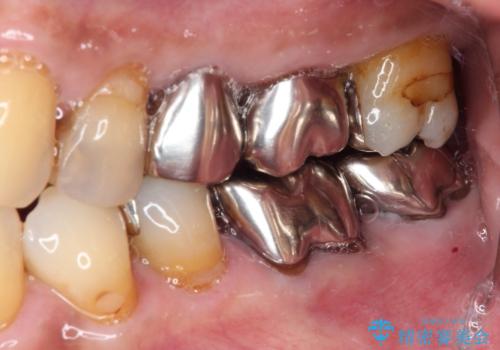

虫歯の範囲が大きく、部分的な詰め物では対応が難しいため、オールセラミッククラウンにて補綴することとしました。

外見からはあまり大きな虫歯があるようには見えなくても、X線検査をすることで、詰め物の下に虫歯が広がっていることは多々あります。

定期的に歯科医院を受診し、早期発見・早期治療をすることで、歯の神経を残す治療が可能になります。